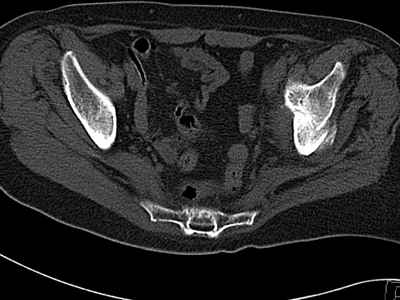

Уважаемые коллеги, возник вопрос по лечению нашей пациентки 60 лет. Около года назад множественная травма: в том числе Т-образный перелом вертлужной впадины. На сегодняшний день сращение отломков имеется на ограниченных участках, имеется дефект задней колонны вертлужной впадины. Движения неплохие, ходит с костылями, приступая на ногу. По мнению эдопротезистов при установке антипротрузионного кольца или октопуса не хватит костного материала и необходимо перед протезированием выполнить реконструкцию впадины, иначе чашка протеза неминуемо выпадет.Просьбы поделиться положительным и отрицательным опытом протезирования в подобных случаях.Возможно ли обойтись без реконструкции?Или лучше с ней?С уважением РАВ.